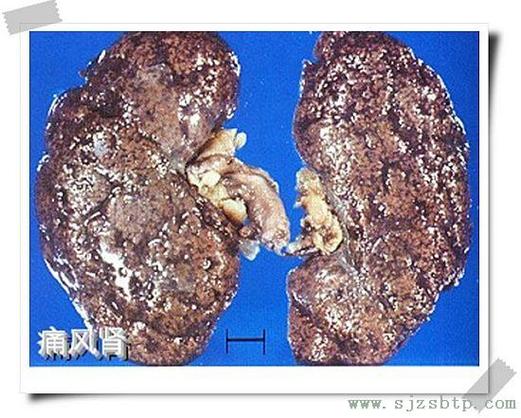

痛风是一种由于尿酸水平过高导致的疾病,尿酸是身体代谢嘌呤(一种存在于许多食物中的化合物)时产生的废物,当尿酸水平过高时,它会在血液中积累,并形成晶体,这些晶体可以在关节、软组织和肾脏中沉积,导致痛风发作。

| 尿酸水平 | 痛风患者的尿酸水平通常较高,这增加了形成肾结石的风险,尿酸晶体可以沉积在肾脏中,形成肾结石。 |